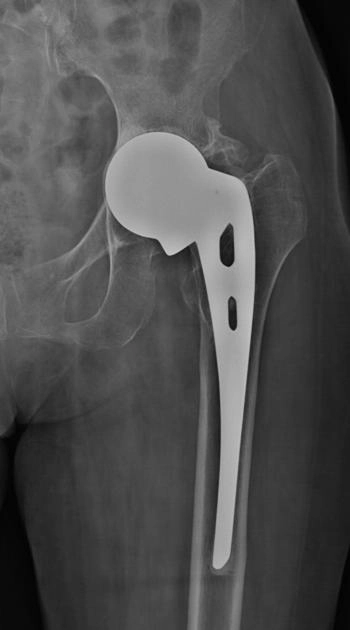

Thay khớp háng toàn phần (Total Hip Arthroplasty - THA)